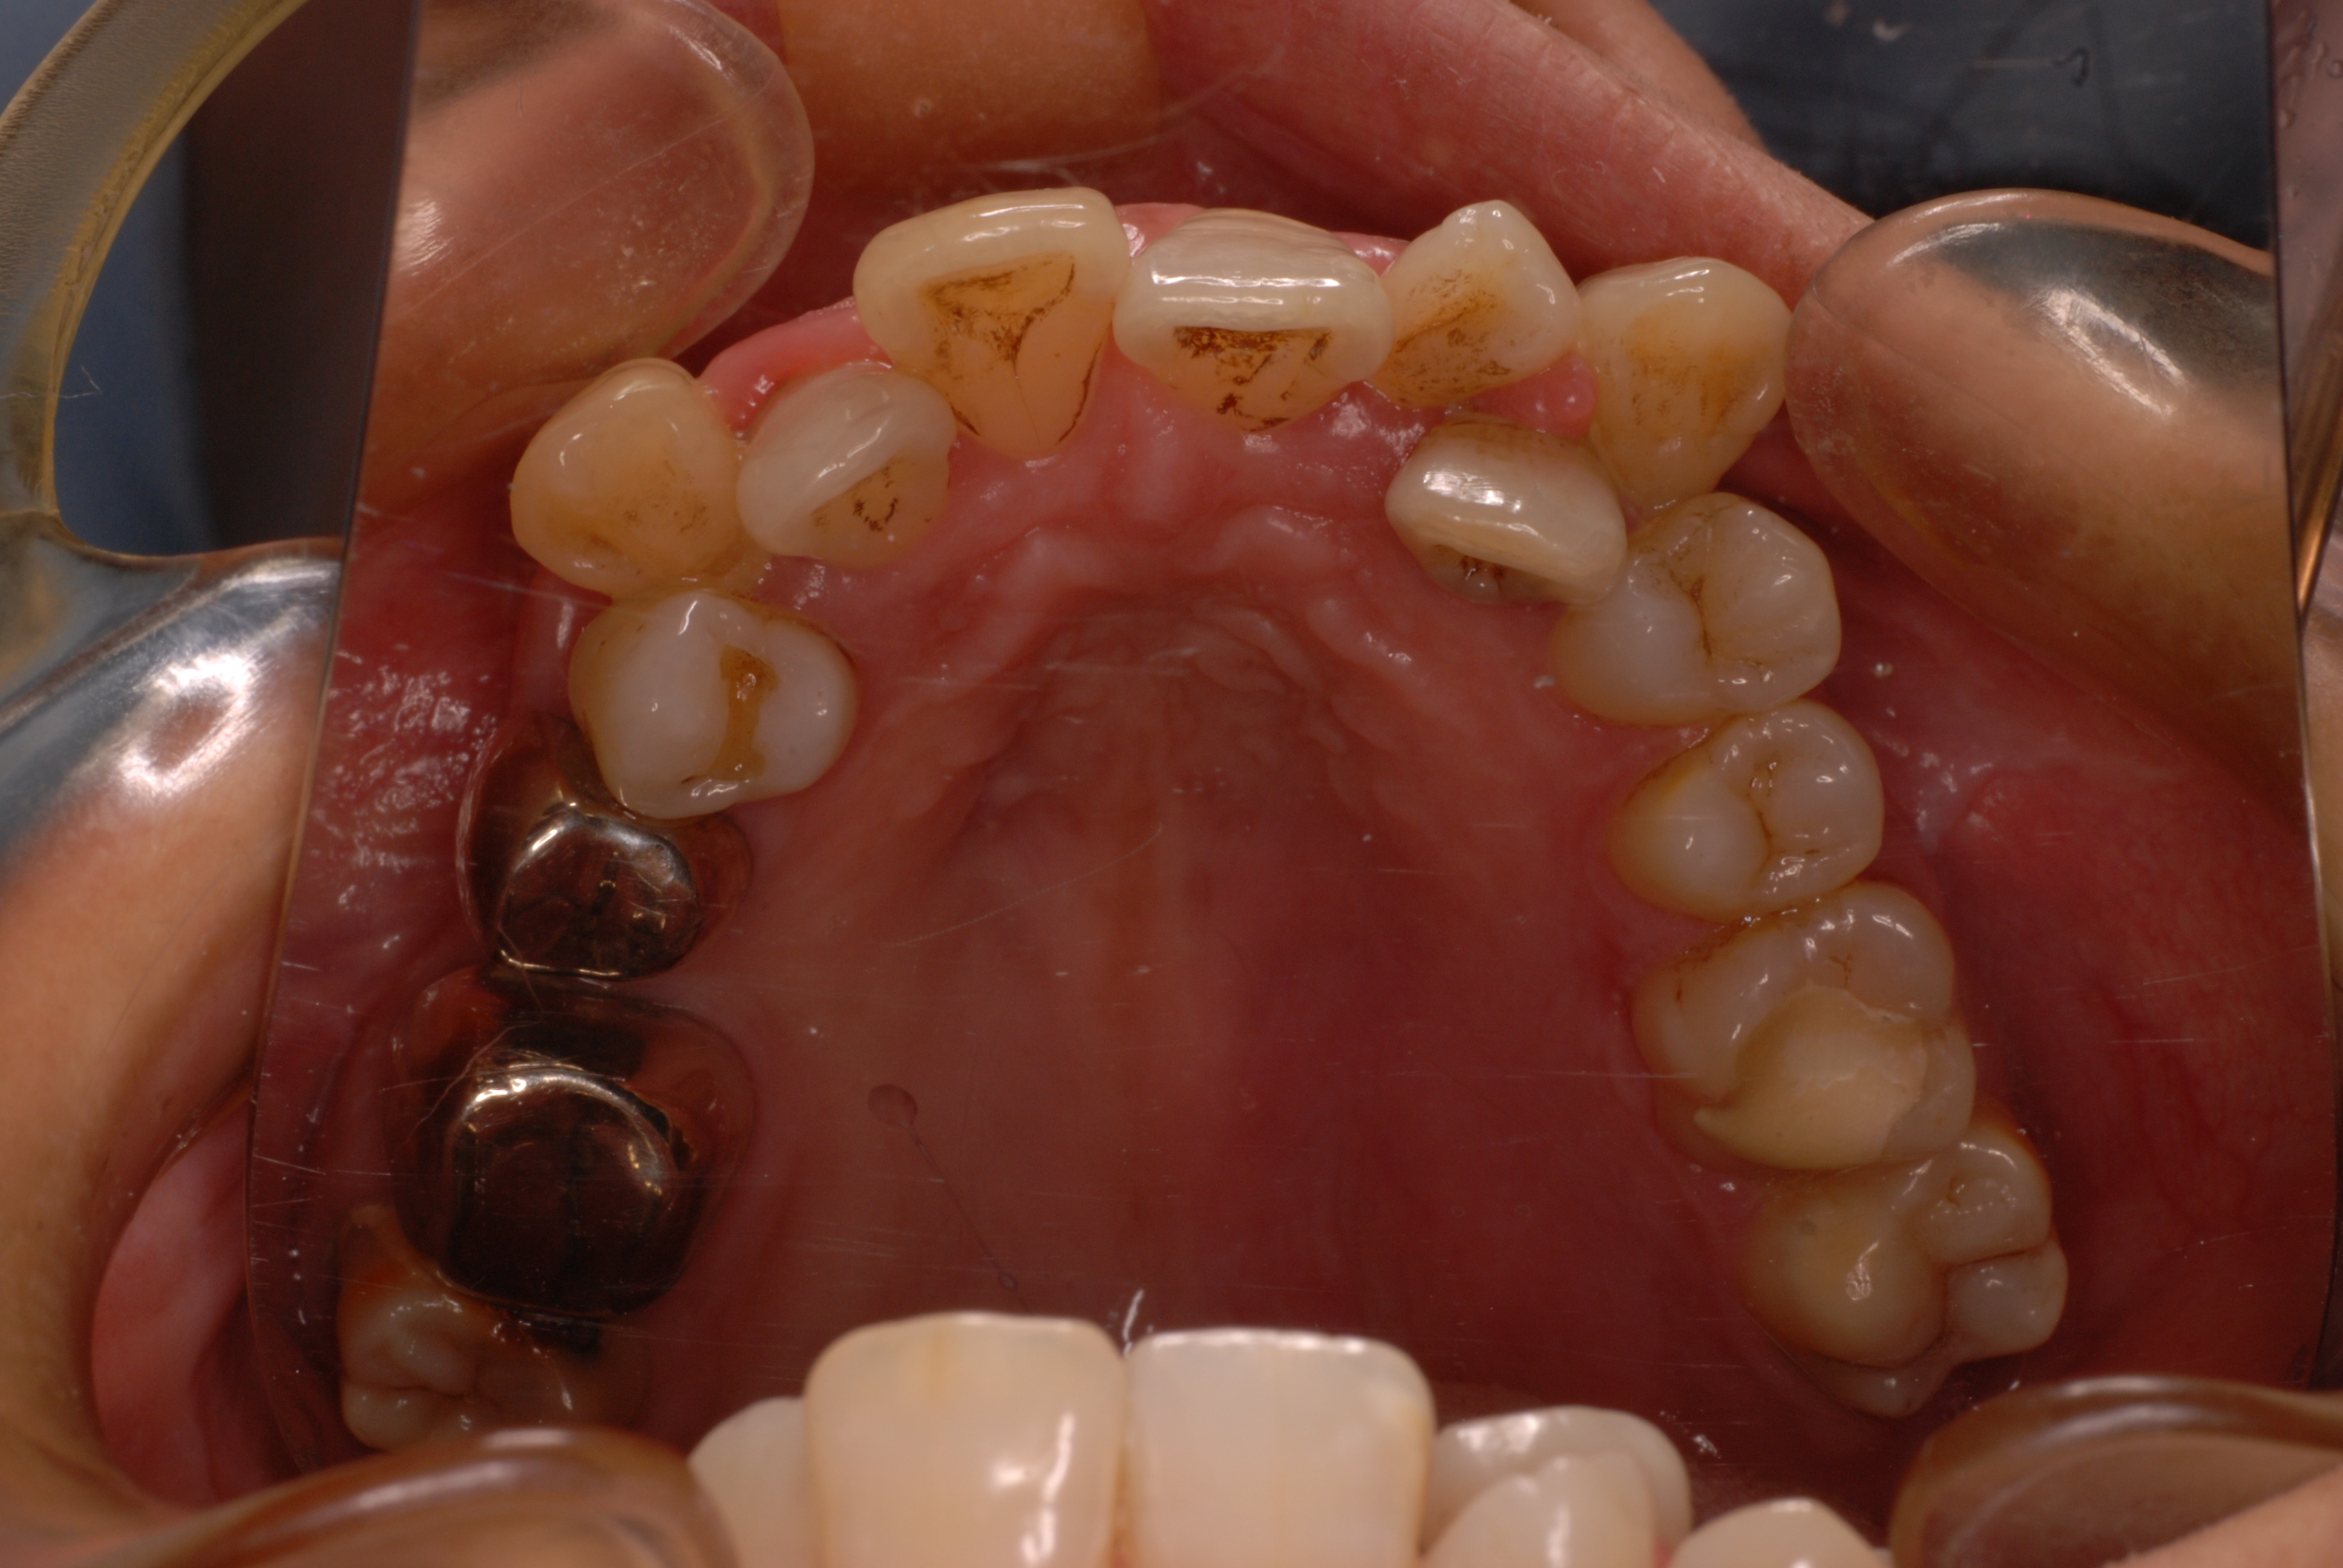

下の写真の方は虫歯と歯の間の歯周病が酷かったのです。

虫歯の治療も完全にできませんし、歯の位置が悪く又重なっている為に歯周病が治らずに説得に数カ月を有した後に矯正することになりました。

矯正治療一ヶ月後です。歯並びのガタガタはすぐよくなっています。